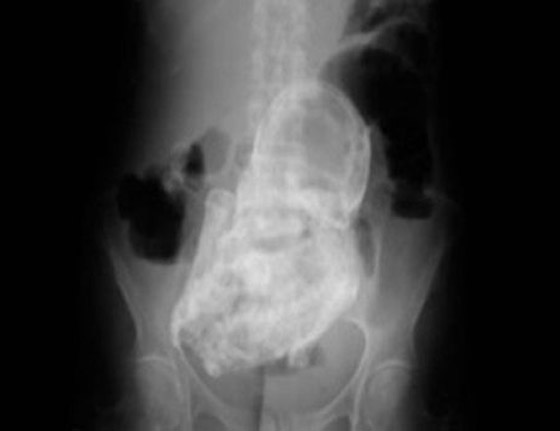

"اللي يعيش ياما يشوف".. ينطبق هذا المثل على واقعة شهدتها المكسيك وبطلتها كانت امرأة ثمانينية! فقد أدهشت السيدة-التي تبلغ من العمر 84 عاما من دورانجو بالمكسيك- المسعفين عندما اكتشفوا أن آلام البطن التي تشكو منها لم تكن إلا جنينا محنطا في رحمها منذ ما يزيد عن 4 عقود.

وبحسب ما ورد في صحيفة بريطانية، فإن المرأة ذهبت إلى عيادة الصحة العامة بسبب آلام مبرحة في بطنها، وبالفحص وجدوا أنها تحمل جنينا لم يكتب له أن يولد منذ 40 عاما. ويعتقد الأطباء أن الجنين قد تكلس، في حدث نادر للغاية يسمى "الجنين المتحجر أو المتكلس".

وعادة تنشأ الظروف المفجعة لهذه الحالة النادرة عندما يموت الجنين أثناء الحمل في البطن، ويكون كبيرا جدا بحيث لا يمكن للجسم امتصاصه، فيتكلس من الخارج كجزء من تفاعل جسم غريب، مما يحمي جسم الأم من الأنسجة الميتة للجنين ويقيها من العدوى.

ويعتقد المسعفون أن الطفل مات وتحنط في الأسبوع الأربعين من الحمل، بعد أن توقف عن النمو بشكل طبيعي. وأضافت التقارير أنه من غير المرجح أن تكون الأم قد تلقت الرعاية المناسبة في أثناء الحمل قبل حوالي 40 عاما.